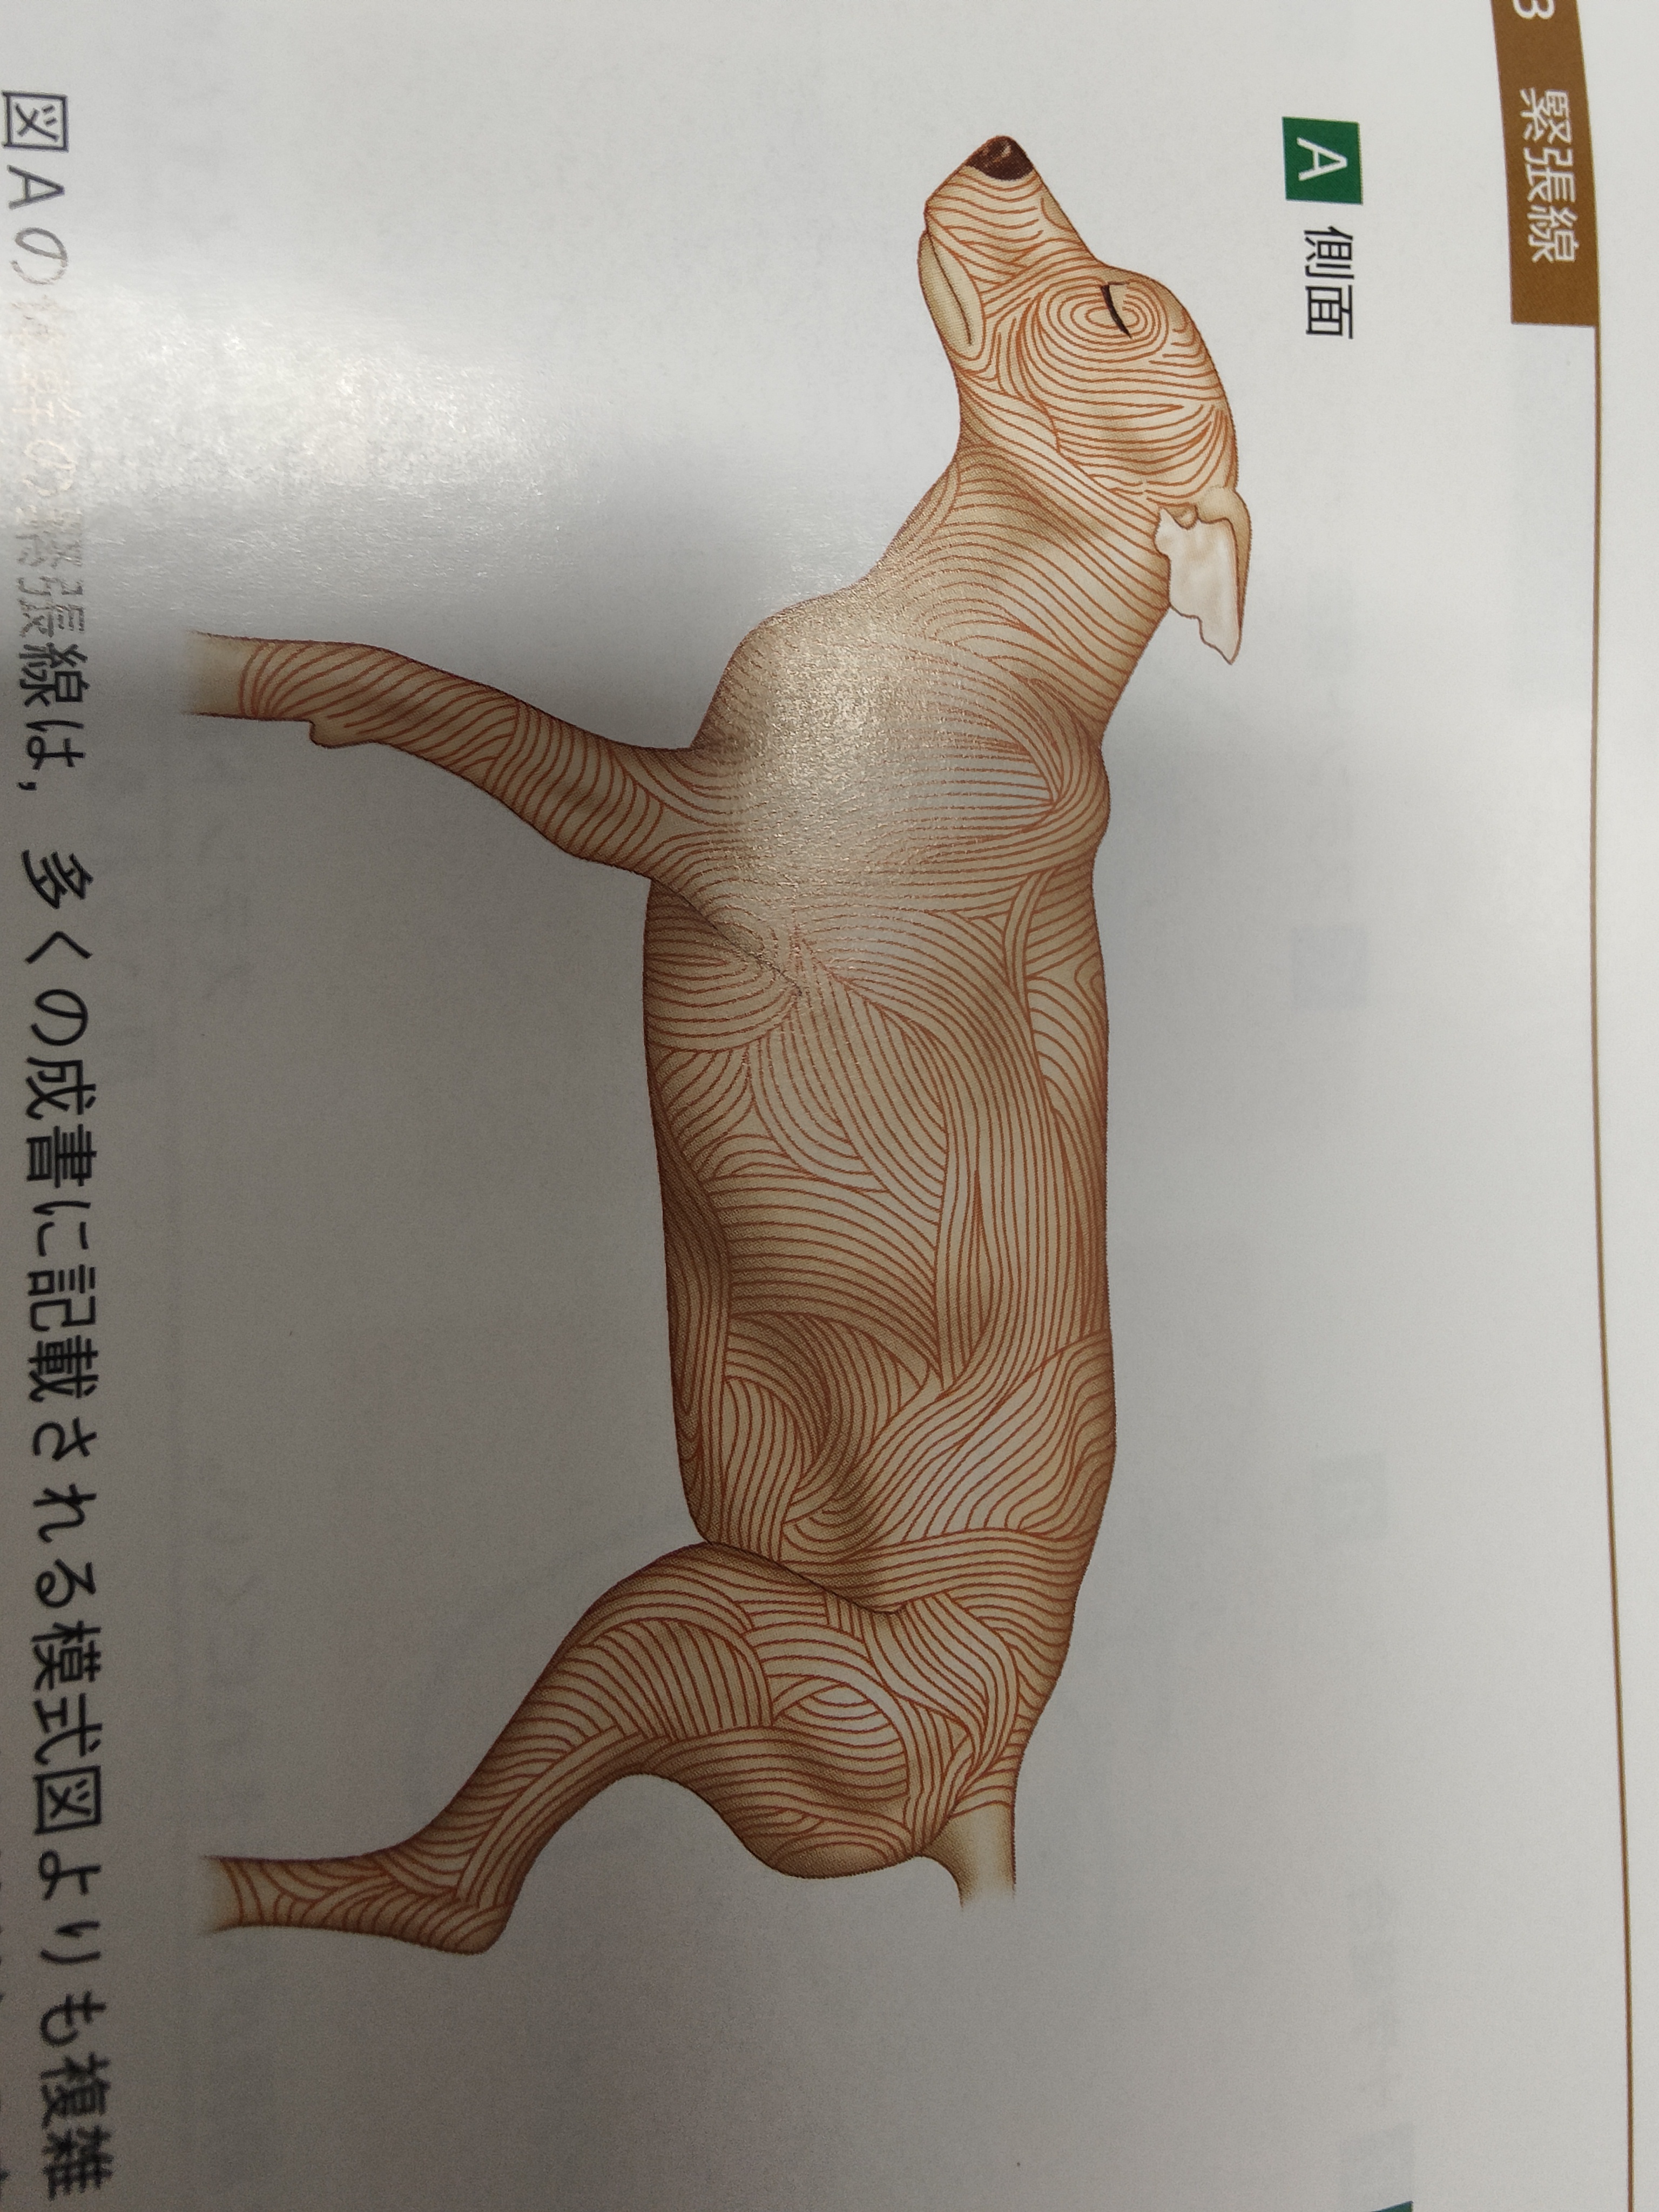

血管とかを、皮膚の伸びる線を考え

皮膚の下の皮筋の走行考えて切開and縫合考え